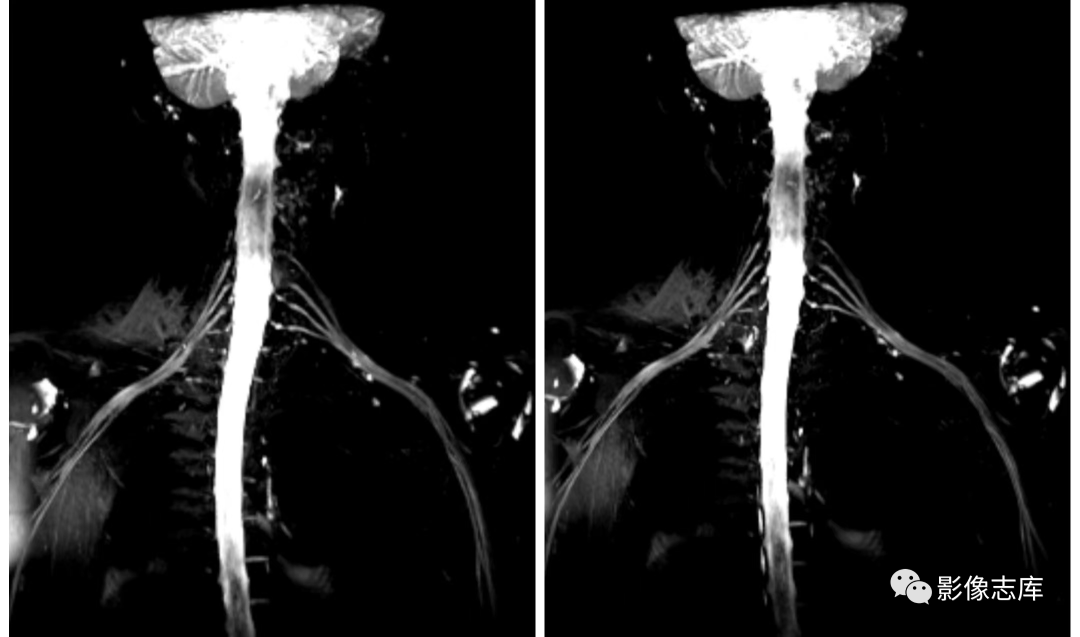

在臂丛神经扫描中,根据不同设备比如1.5和3.0T,我们选择的序列不同,总体原则就是跟扫描MRCP一样,凸显胆道系统,抑制背景组织,扫描臂丛神经也是一样的,凸显臂丛神经,抑制背景组织包括软组织、血管以及淋巴结等,因此也主要使用重T2加权成像,压脂主要选择STIR,但是有时候STIR压脂效果也不是太理想,因此还可以结合其他压脂技术,以西门子3.0T vida设备为例我们通常选择以下序列:

不打药和打药区别:利用重T2结合脂肪抑制STIR序列,可达到一定背景组织抑制的目的,但是血管和淋巴结很难将其抑制,为了达到这些组织不被显现,因此引入打药后的T2负性增强原理,由于微小血管和淋巴结可吸收少量对比剂,对比剂可缩短T2弛豫时间,因此通过打药后的T2加权可达到微小血管和淋巴结抑制的目的。

背景抑制:打药后进行T2 SPACE STIR cor 扫描,使背景抑制更彻底;

可实现各向同性:可进行3D等体素,扫描后可进行多方位重建,多角度观察臂丛神经;